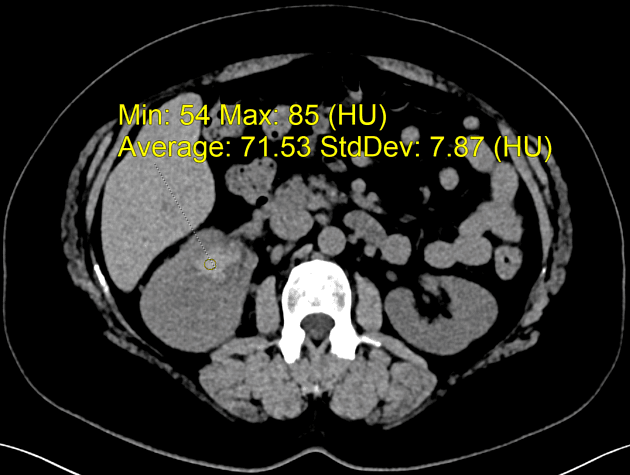

- Một khối ngấm thuốc kích thước 28 x 20 x 22 mm nằm ở phần trên của hệ thống đài bể thận phải.

- Trên cắt lớp vi tính (CT), tổn thương thường có mật độ mô mềm với mức độ ngấm thuốc nhẹ, thường thấp hơn đáng kể so với nhu mô thận hoặc ung thư tế bào ống thận.

- "Trên CT, ung thư biểu mô niệu quản thường cho mức độ ngấm thuốc nhẹ hơn nhu mô thận, giúp phân biệt với ung thư tế bào ống thận."

Ung thư tế bào biểu mô niệu quản thận khởi phát từ biểu mô chuyển tiếp của đài bể thận và được phân loại mô học là một dạng ung thư biểu mô niệu quản. Bệnh chiếm khoảng 5–10% các ung thư thận, hiếm gặp hơn nhiều so với ung thư tế bào ống thận. Trên CT có cản quang, tổn thương điển hình là khối mô mềm nhỏ trong đài bể thận với mức độ ngấm thuốc nhẹ đến trung bình. Do vị trí và đặc điểm ngấm thuốc không rõ rệt, khối u dễ bị bỏ sót, đặc biệt khi không có giãn đài bể thận. Chẩn đoán thường được nghĩ đến ở bệnh nhân tiểu máu không đau, nhất là những người có yếu tố nguy cơ như hút thuốc hoặc tiếp xúc nghề nghiệp với amin thơm. Chẩn đoán xác định cần dựa vào sinh thiết hoặc mẫu mô sau phẫu thuật. Điều trị chủ yếu là cắt thận – niệu quản toàn bộ kèm cắt vạt bàng quang, tùy theo giai đoạn bệnh và tình trạng bệnh nhân.